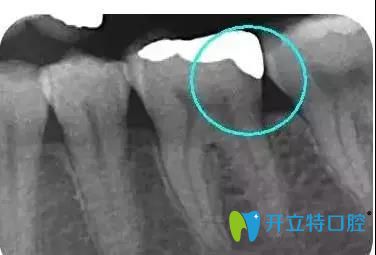

擅長項(xiàng)目:種植牙、牙周病治療、牙體牙髓疾病診療、牙齒瓷貼面、瓷嵌體、全口活動義齒、牙槽外科手術(shù)、各種復(fù)雜智齒的拔除等。

南昌輝煌口腔鄧云蟬醫(yī)生介紹嵌體補(bǔ)牙后注意事項(xiàng):